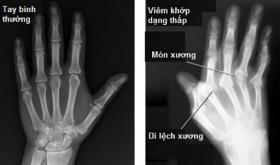

Cách chữa viêm đa khớp dạng thấp khỏi lâu dài